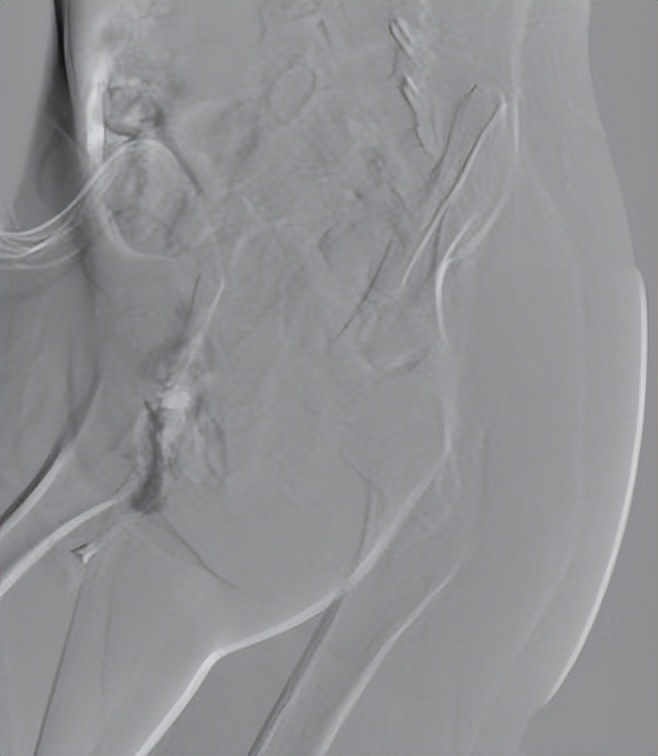

患儿全麻后,进行了经动脉的穿刺造影,可见臀部病灶处可见异常染色,经皮穿刺造影可见病灶处造影剂弥漫分散,诊断静脉畸形明确。进行了硬化治疗。术后第二天出院,出院后口服利伐沙班药物治疗。

经皮穿刺病灶处,可见异常染色